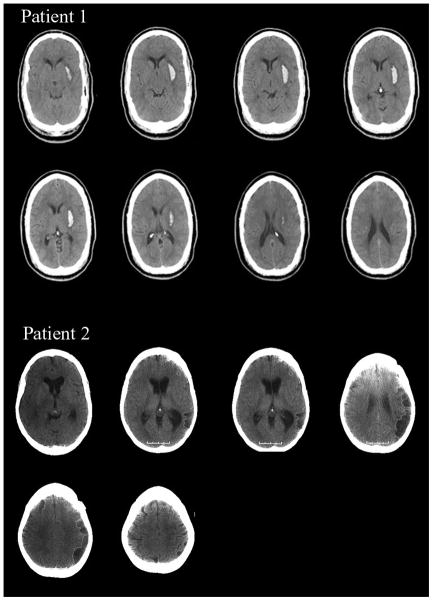

Patient 1 was a 39-year-old right-handed man with thirteen years of formal education who suffered a hemorrhagic stroke one week prior to testing. A CT scan obtained two days post-stroke revealed a hemorrhage in the left putamen (Figure 1, volume = 10.14 cc). Patient 1 suffered mild right hemiparesis but was not aphasic. His Western Aphasia Battery (Kertesz & Poole, 1974) Aphasia Quotient was 95.8 (normal range = 93.8–100). He was oriented to time, person and place but demonstrated acute deficits in arousal, often falling asleep during rehabilitation. Neglect was evident according to the Behavioural Inattention Test (BIT: (Wilson, Cockburn, & Halligan, 1987)) (124/146; neglect < 129), where right-sided omissions were observed on both cancellation and drawing tasks. Right neglect was also evident on line bisection. Patient 1 neglected approximately 10 percent of the line’s total length (20 cm) (Mennemeier et al., 1997). Finally, patient 1 could not complete part B of the Trail Making Test (Army Individual Test Battery, 1944) because he could not alternate between number and letter consistently.

Figure 1.

MRI scans of patient 1 indicating a putaminal hemorrhage in the left hemisphere. CT scans of patient 2 indicating hypodensities involving temporo-parietal cortex in the left hemisphere. Both scans are in radiological format (R=L, L=R).

Patient 2 was a 45-year-old right-handed woman with sixteen years of formal education who suffered a stroke approximately two years and three months prior to testing. A post-stroke CT scan revealed hypodensities in the left hemisphere presumably due to cerebral infarction (Figure 1). Mapping the lesion us ing Damasio templates (Damasio & Damasio, 1989) indicated clear involvement of temporo-parietal cortex, i.e., Brodmann’s Areas 21, 37, 22, 40, & 39. Patient 2 had expressive aphasia (Western Aphasia Battery Aphasia Quotient = 55.7) without hemiparesis. Her ability to follow sequential commands was poor (40/80). However, this appeared to reflect output rather than comprehension, per se, as her fluency was 0/10, repetition was 46/100, object naming was 42/60, and animal naming was 5/20. In contrast, information content was 10/10, auditory word recognition was 54/60 and yes-no responding was 57/60. Though patient 2 had difficulty speaking, she could express herself in writing. She did not evidence neglect on the BIT (142/146) and did not evidence any overt deficits in arousal. She too could not complete part B of the Trail Making Test as she was slow and made errors alternating between letter and number.